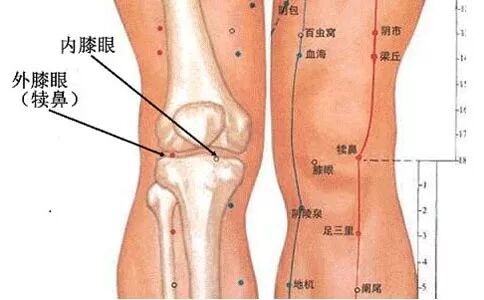

膝关节骨性关节病以中老年阶段为发病高峰期,尤其是肥胖的女性,发病率更高。该病的主要表现为:膝关节持续的运动性疼痛,即下蹲痛,上下楼梯痛,尤以下楼梯更甚,并有功能障碍,常受天气影响。其特点是:病程长,病情时好时坏,迁延难愈。该类患者摄片时多有膝关节的退行性改变,包括髌骨软化,髌骨上下缘骨质增生,软骨破坏,骨刺形成,关节间隙狭窄,关节面不平等改变。据此,传统观点认为:膝关节骨性关节病是由于局部骨质增生,引起关节间隙狭窄,从而形成运动性疼痛和功能障碍,即骨性观点。依据这一理论,该类患者若要得到彻底治愈,势必应行开放性手术切除骨赘,才能解除疼痛,然而在临床实践中,相当一部分患者并未达到理想效果。而且,通过长期临床观察发现,大部分患者膝关节的X线退化性征象和膝部疼痛并没有平行关系。

我院在长期的临床实践中,最终认识到:膝关节腔内滑膜关节软骨及周围软组织(内外侧副韧带、髌下脂肪垫、髌韧带及股四头肌腱膜等)慢性损伤,造成关节内外炎性介质释放,炎性物质在局部堆积,刺激滑膜,使滑膜充血、肿胀,异常分泌滑液,加重关节肿痛;刺激神经末梢引起疼痛。长期慢性炎症作用,使得膝关节内炎性物质大量堆积,膝关节周围软组织出现粘连、挛缩,从而形成多个局部高张力点,出现异常应力,破坏了膝关节生物力学平衡,导致膝关节代偿性骨质增生,并出现关节失稳变形功能障碍。